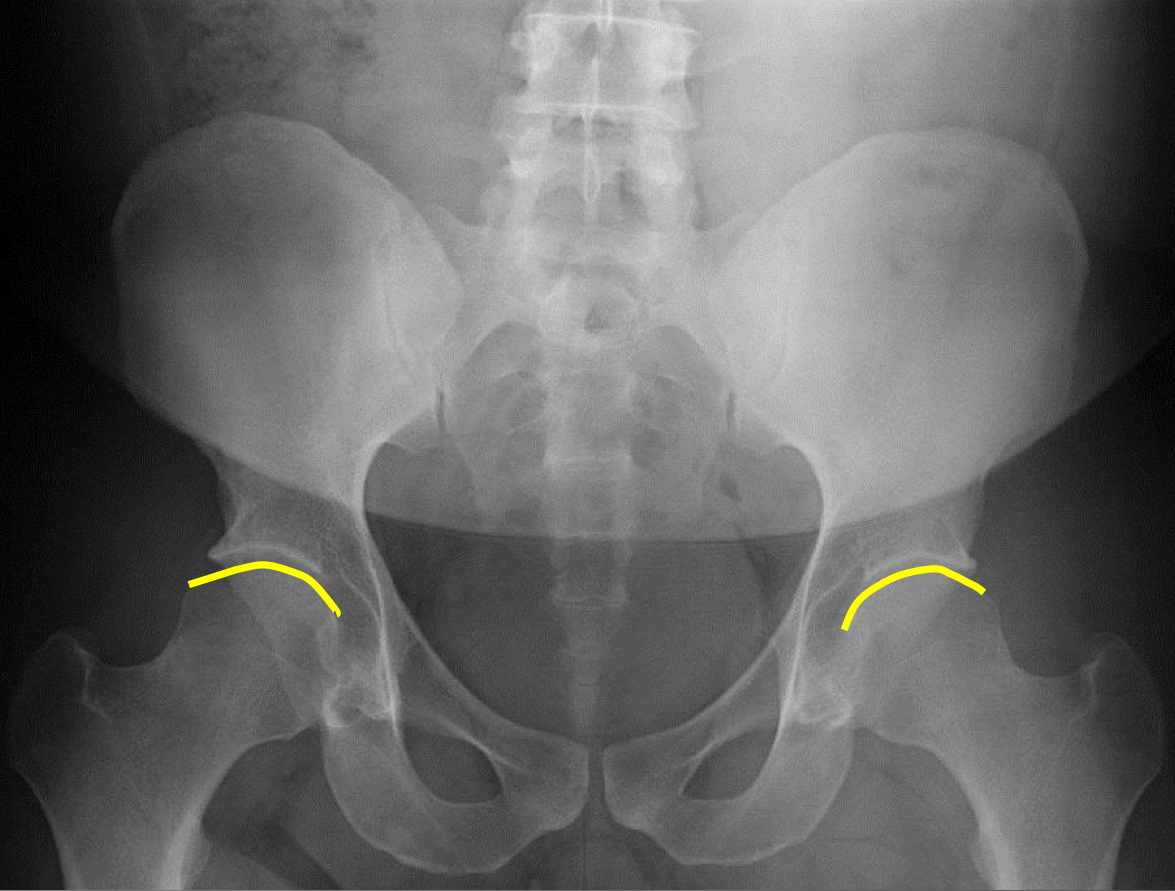

What view is this?

AP (Anterior to Posterior) LumboPelvic

What is this?

Femur Heads

What is this?

Superior Iliac Crests

What is this?

Lateral Iliac Crests

What is this?

Ischial Tuberosites

What is this?

Obturator Foramen

What is this?

S2 Tubercle

What is this?

Pubic Symphysis

What is this?

Sacral Groove

What is this?

Lateral aspect of sacrum

What is this?

Medial Aspect of Ilium